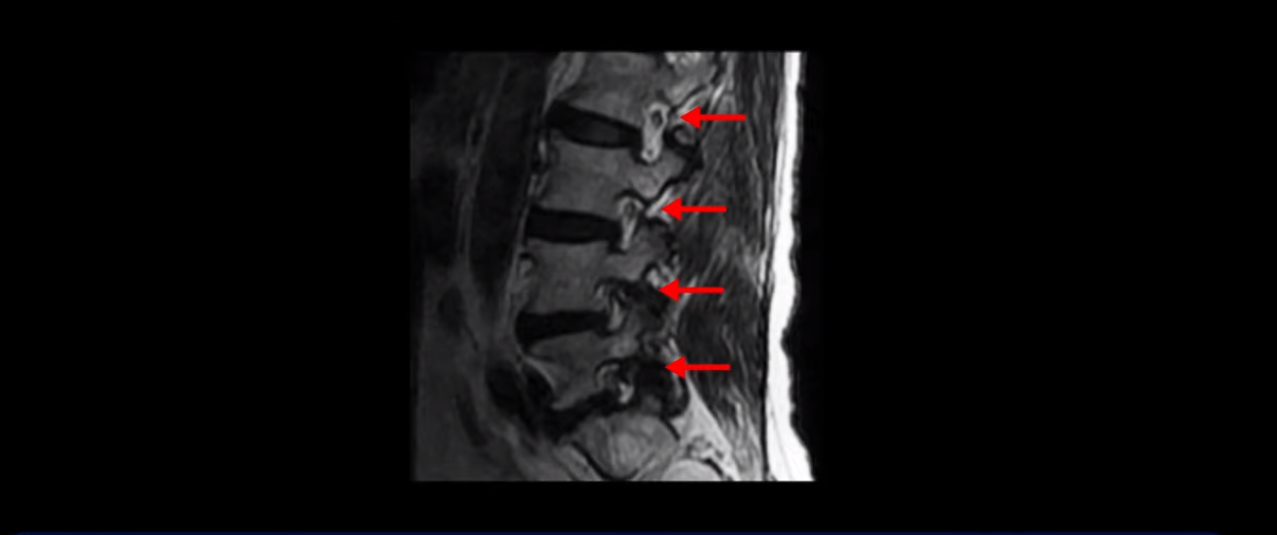

이 환자분은 협착증으로 왼쪽 다리 방사통과 발목 마비, 즉 까치발이 안 되고 뒷꿈치로 서지 못하는 족하수 증상이 있어서 내시경 감압술을 1년 반 전에 받았는데 수술 후에 오히려 다리 방사통도 더 심해지고 다리 마비 증상 즉 발목 힘빠짐이 더 심해지고 종아리 근육이 많이 빠져 양쪽 다리가 짝짝이 되신 환자분입니다.

이분 MRI를 보시면 허리 세 마디가 퇴행은 있으나

척추관도 3번 4번

4번 5번

5번 1번

전부 다 충분히 넓고 왼쪽 다리 쪽으로 신경이 나가는 추간공도 전부 다 충분히 넓은 상태입니다.

신경이 눌려 보이지 않는 겁니다. 그러니까 수술 후 MRI를 보고 모든 병원이 전부 다 ‘수술은 잘돼 있다’, ‘아무것도 해줄 게 없다’ 그냥 기다리라고만 얘기했다고 합니다. 신경외과, 정형외과, 재활의학과가 서로 다른 과로 전과시키면서 다들 아무것도 해줄 게 없다고 하니 희망을 잃은 상태였다고 했습니다.